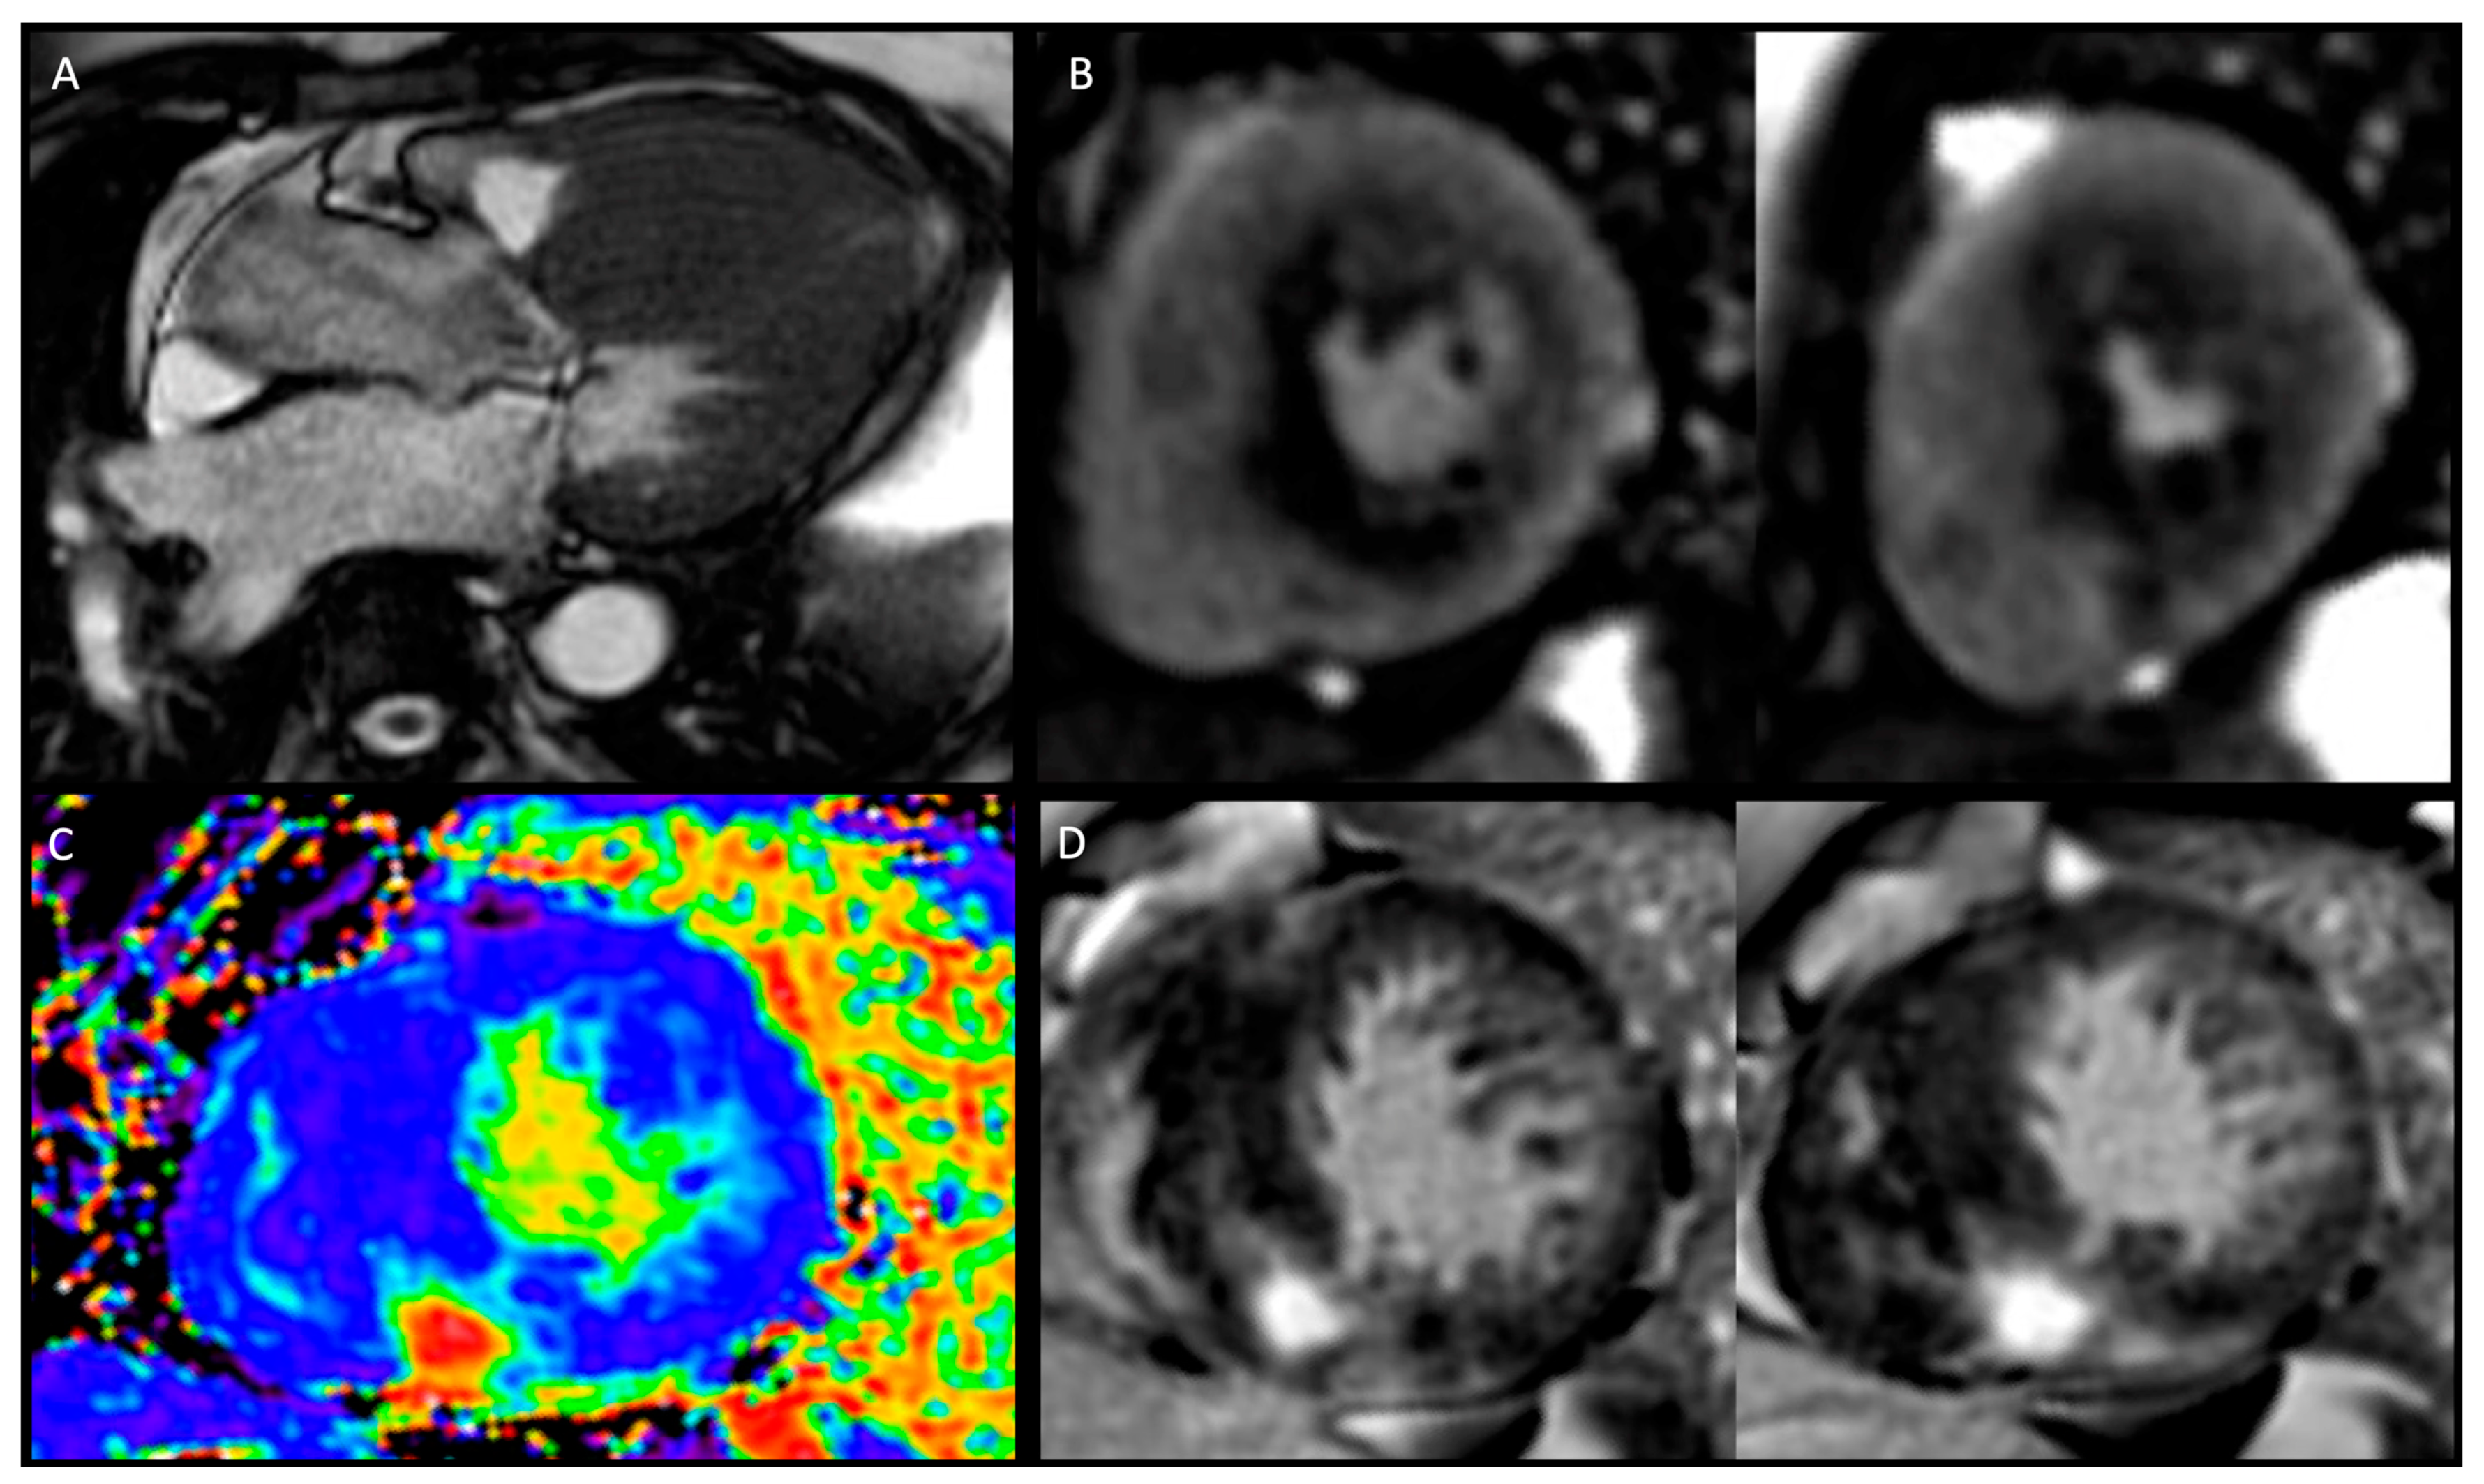

- Athlete’s heart: in response to chronic high-intensity physical activity, the cardiovascular system activates a series of adaptative physiological mechanisms defined as the athlete’s heart, including a constellation of changes with increased biventricular mass, volume, and wall thickness. A stepwise approach to the cardiovascular assessment of athletes is essential to make sense of overlapping clinical phenotypes and eventually provide a correct differential diagnosis between HCM and adaptative cardiac response to exercise. Twelve-lead ECG enhances the sensitivity of the screening process by allowing early detection of cardiovascular conditions distinctively manifesting with ECG abnormalities. Echocardiography has a pivotal role in differentiating physiologic and pathologic responses to exercise, namely athlete’s heart, from HCM. Combining different methods, such as 2D and 3D measurements of cardiac size, volumes, wall thickness, mass index, tissue velocity, and myocardial strain imaging, cardiac ultrasound allows comprehensive morphologic and functional evaluation of the heart and distinction between physiologic and pathologic remodelling. In the presence of abnormal, uncertain, and/or controversial findings from the upstream diagnostic work up, CMR imaging can help distinguish between exercise-induced cardiac remodelling and cardiovascular pathology. CMR represents the current gold standard in the non-invasive assessment of cardiac morphology and quantification of volumes and flow and offers the opportunity for advanced myocardial tissue characterisation with excellent accuracy and precision [24,25].